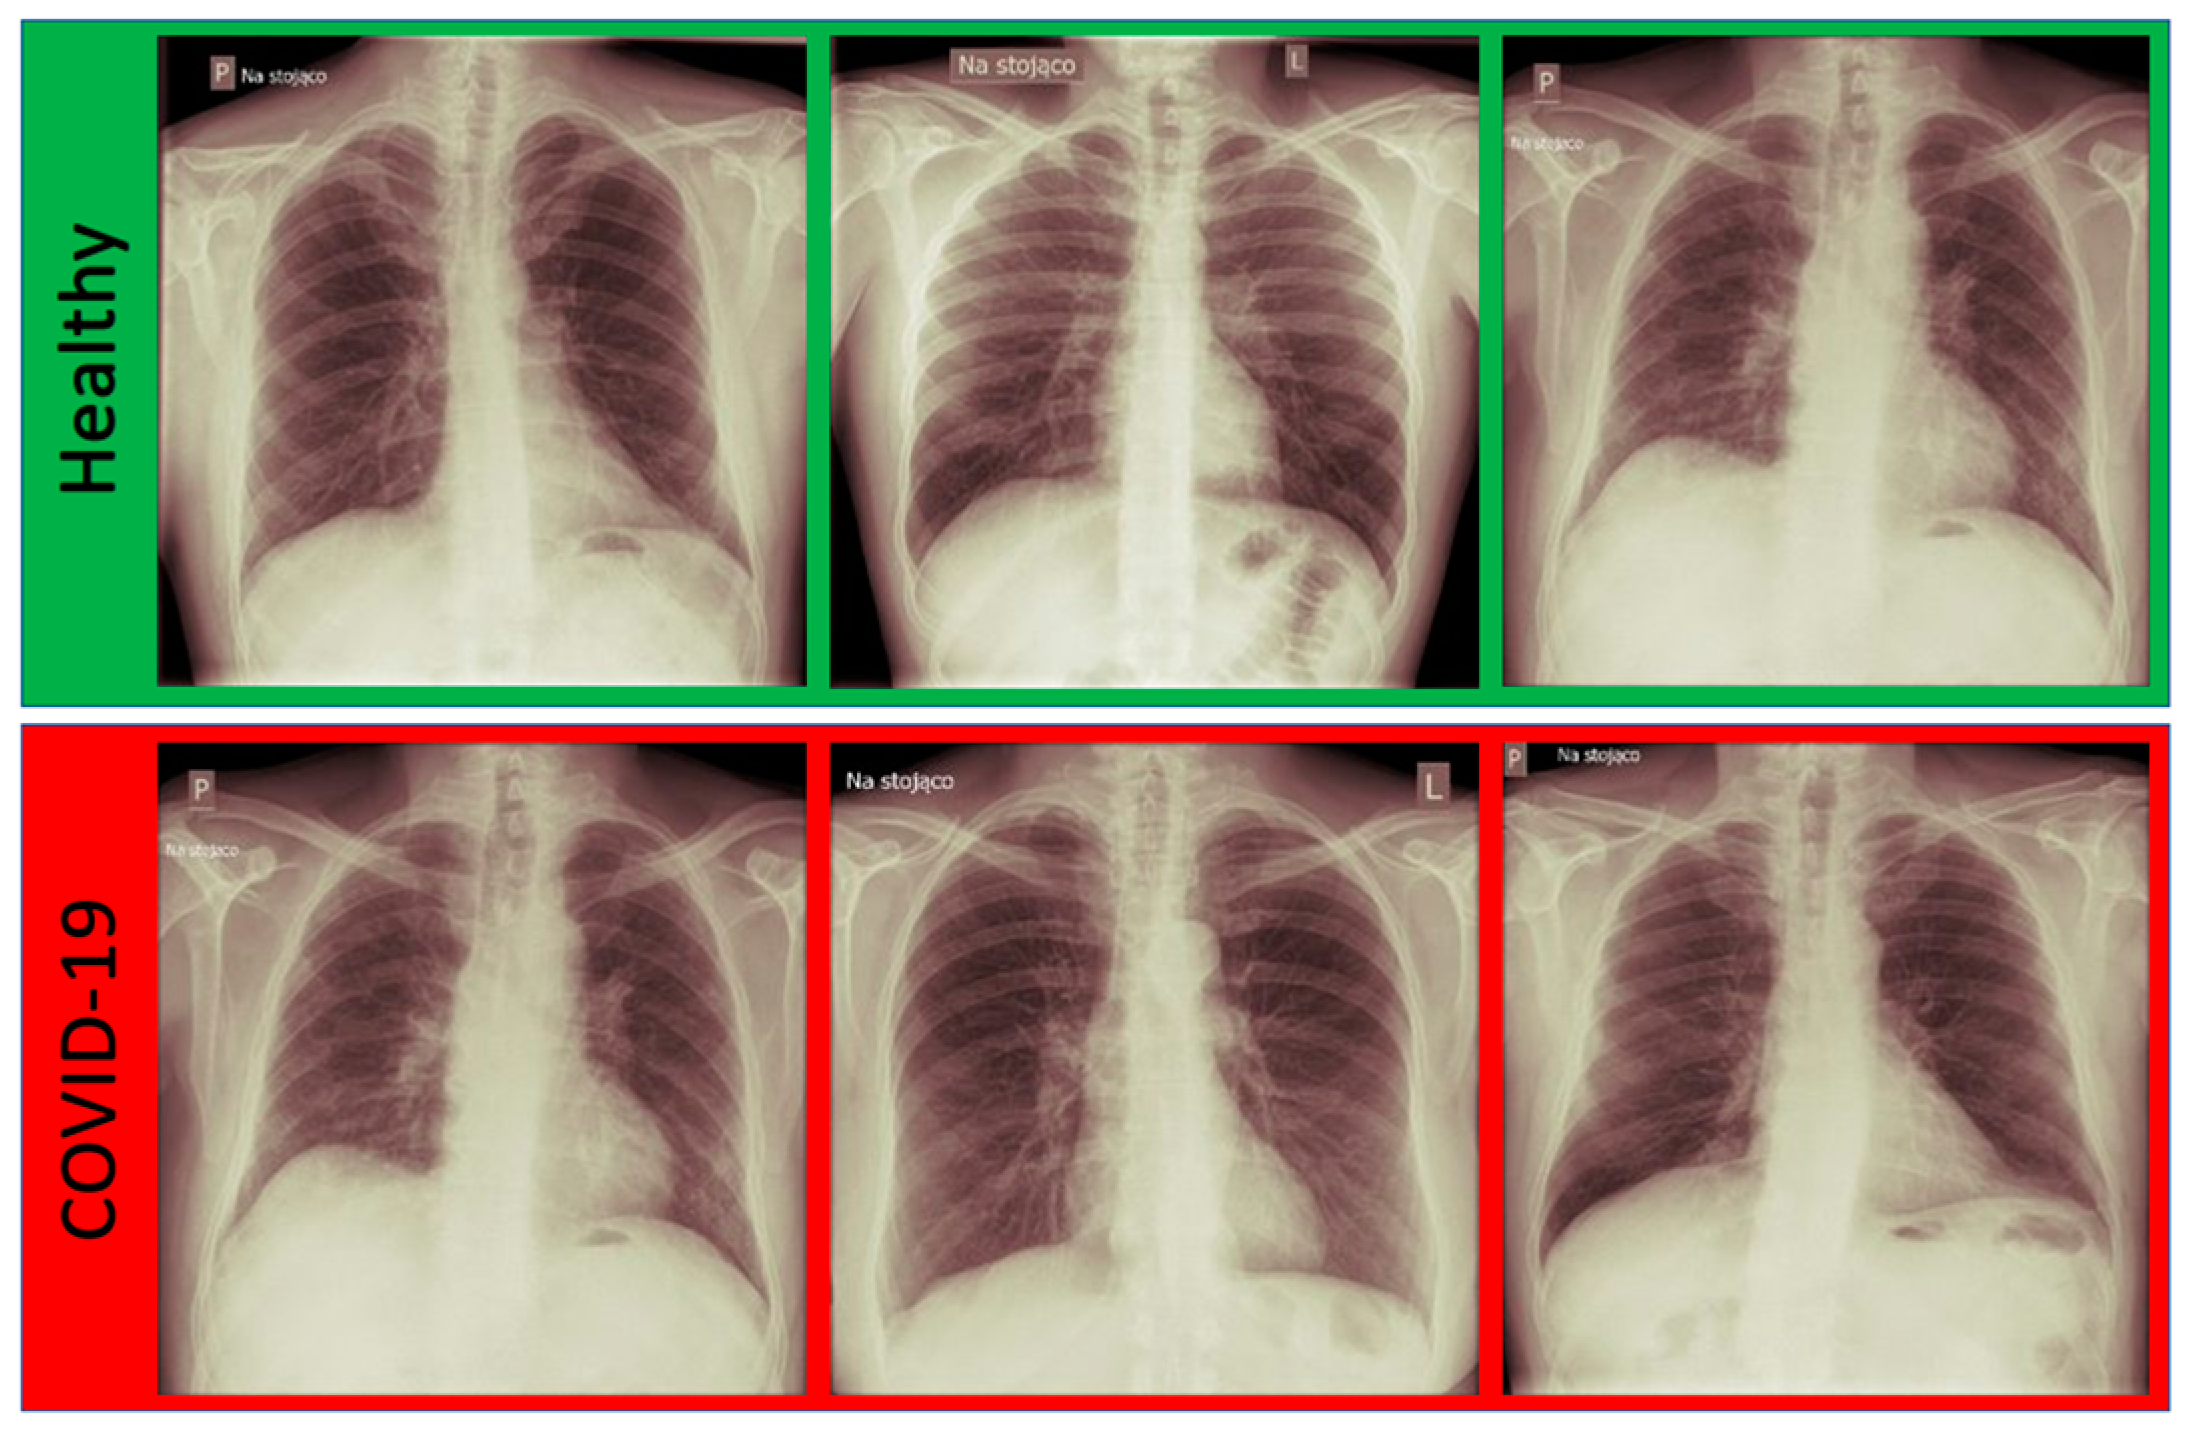

3.1. Dataset

- We obtained a new dataset containing samples from confirmed COVID-19 cases as well as from uninfected patients. The infection status of both groups was confirmed by a PCR test. We performed an augmentation in order to increase the dataset’s size.